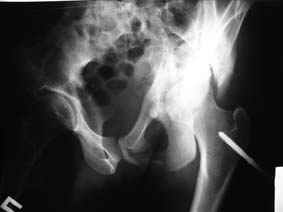

Все-таки надо бы начать не с КТ, а с обзорного снимка таза и косых проекций впадины.

Это обзорные и косые снимки

С уважением,

Leonid

Привет, Леонид. Оскольчатый высокий двухколонный перелом в такие сроки трогать не надо, т.к. это про такие переломы сказано: "кто с ножом на Ж. пойдет тот в ней и останется...".